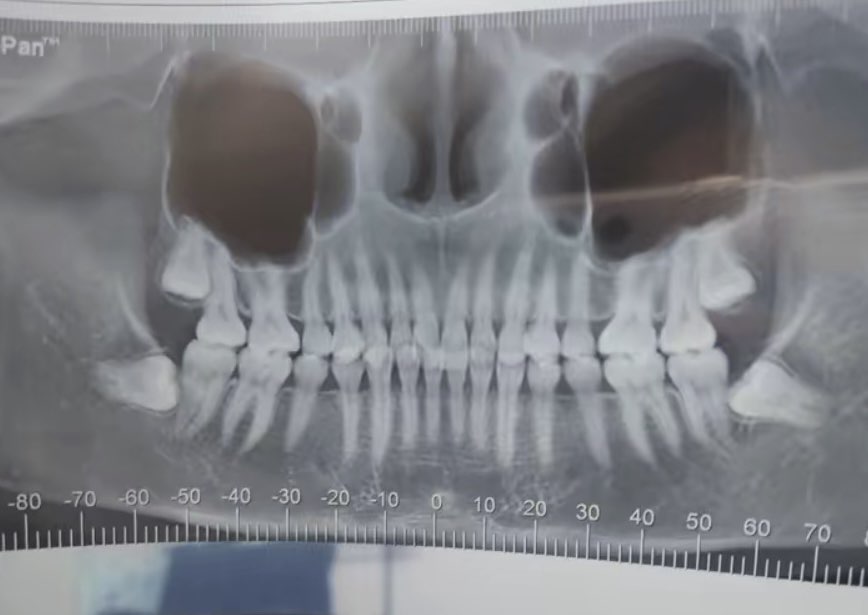

这四颗牙需要破费多少

看看需要苦哈哈的活多久

这个四颗最少4000: iPhoneͻ

出来的便宜,没出来的贵,: iPhoneͻ

上面两颗200一颗,下面两颗1000一颗: iPhoneͻ

这牙根长得太牛了: iPhoneͻ